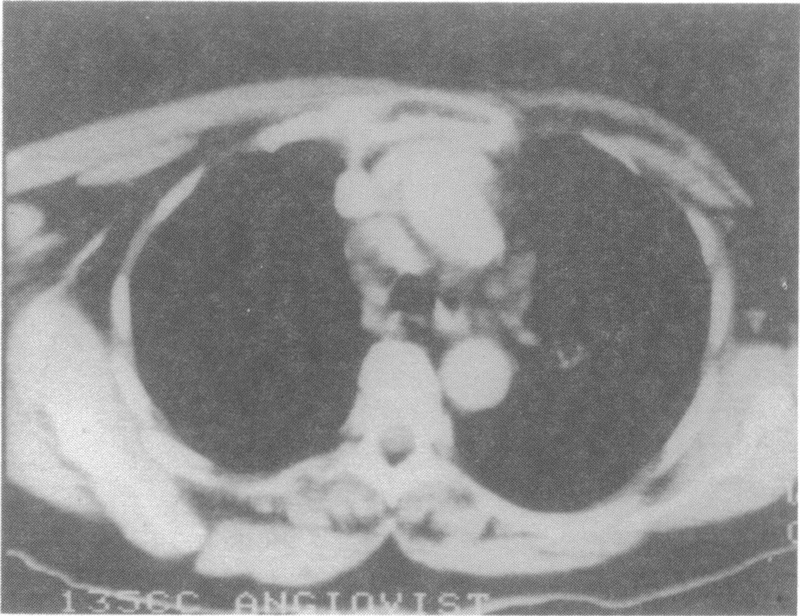

of chronic bilateral maxillary sinusitis (see panel A, below).

Panel A. Radiograph of the paranasal sinuses showing complete opacification of both maxillary sinuses. There is no evidence of bone erosion.